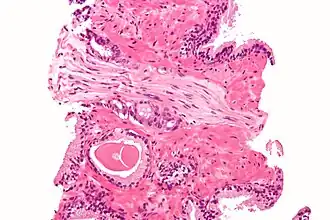

In pathology, perineural invasion, abbreviated PNI, is the invasion of cancer to the space surrounding a nerve. It is common in head and neck cancer, prostate cancer and colorectal cancer.

Unlike perineural spread (PNS), which is defined as gross tumor spread along a larger, typically named nerve that is at least partially distinct from the main tumor mass and can be seen on imaging studies, PNI is defined as tumor cells infiltrating small, unnamed nerves that can only be seen microscopically but not radiologically and are often confined to the main tumor mass. The transition from PNI to PNS is not precisely defined, but PNS is detectable on MRI and may have clinical manifestations that correlate with the affected nerve.[1]

Micrograph demonstrating perineural invasion. HPS stain.